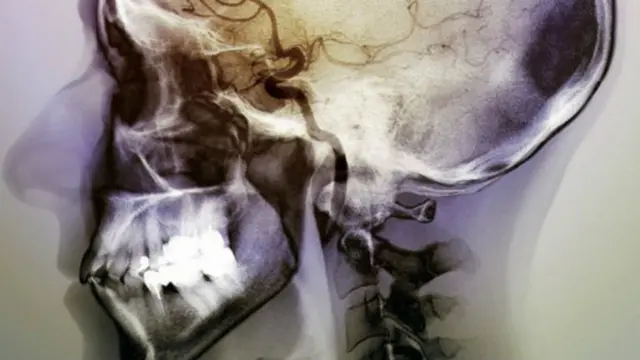

،تصویر کا ذریعہzephyrscience photo library

سائنسدانوں کا خیال ہے کہ انسانی دماغ کا ایک مخصوص حصہ اسے سگریٹ نوشی کی عادت ڈالتا ہے۔

سائنسدانوں کا کہنا ہے کہ فالج سے جن لوگوں کے دماغ کے اس حصے کو نقصان پہنچتا ہے جسے انسولر کورٹیکس کہا جاتا ہے ان کے لیے سگریٹ نوشی چھوڑنا آسان ہوتا ہے۔